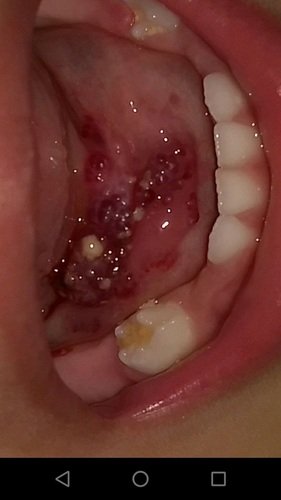

Olá pessoal me chamo Miguel e tnho 5 aninhos, eu nasci com uma doença rara chamada Linfangioma, por conta dela eu tive 3 paradas respiratórias, 2 infecções hospitalares e outras infecções e agravaram meu estado de saúde.

Ja foi diagnosticado que tenho também alguns hemagiomas e por serem doenças raras meu tratamento é muito caro e meu pai que hoje luta sozinho pela minha causa ja que minha mamãe faleceu não tem condições de pagar meu tratamento.

Esse ano de 2021 eu peguei COVID e o tumor reagiu de forma muito negativa por causa disso ele inchou e causou ate mesmo emorragias que me atrasou ainda mais de fazer algum procedimento.